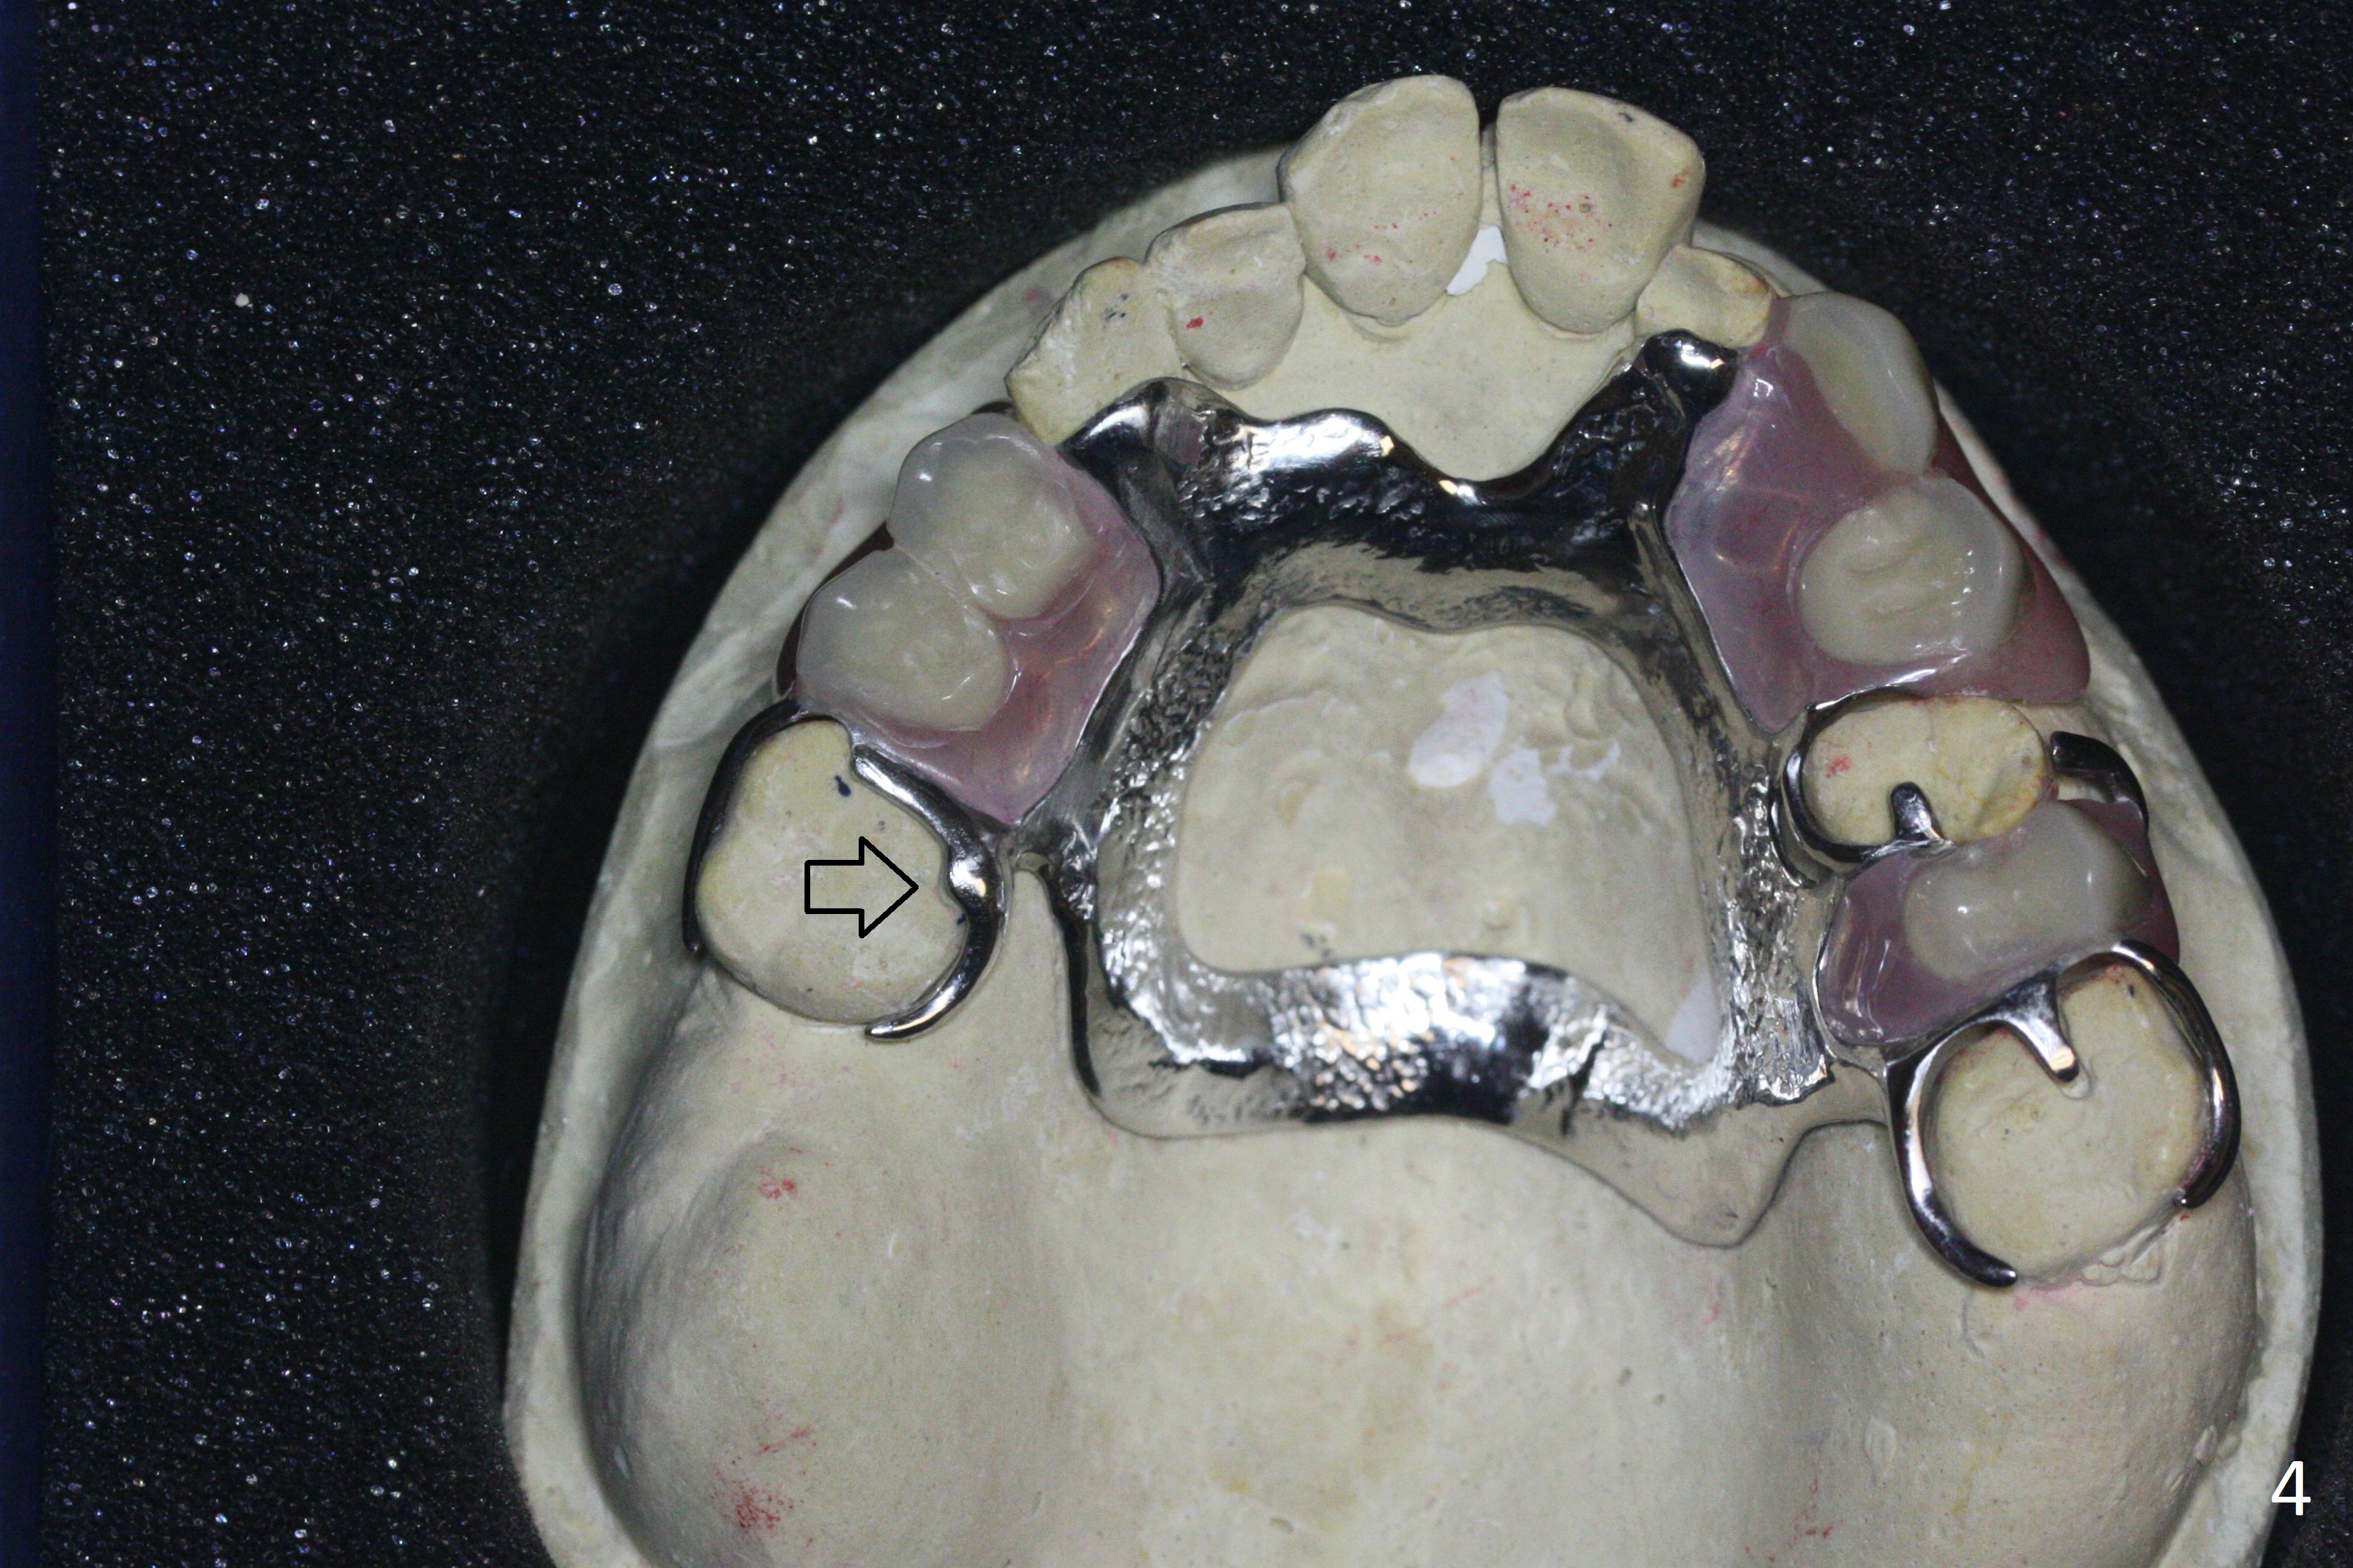

Please redo upper RPD, because it does not seat well in the mouth.  It appears that the clasps at #15 deform (Fig.4).

In our previous model, there is a similar prep at #3 (Fig.3 arrow).  The lingual clasp is somewhat long (Fig4 arrow).  When redoing the case, please shorten the lingual clasp and do not fabricate the buccal one.